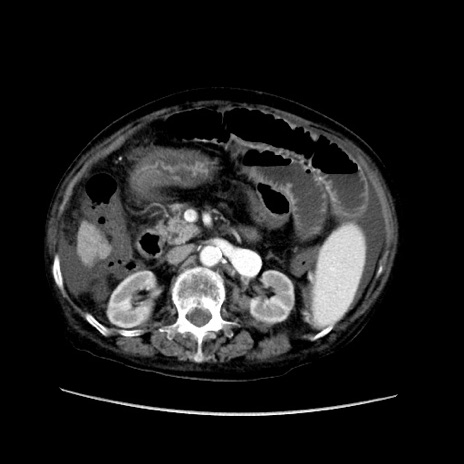

症例31(横断像)

【症例】80歳代 女性

【主訴】腹部膨満感

【現病歴】他院にて肝硬変にてフォロー中。1週間前から便秘、腹部膨満感、臍部腫瘤あり受診となる。

【既往歴】肝硬変

【身体所見】腹部膨隆あり、皮膚変化なし、疼痛なし。

【データ】WBC 4600、CRP 0.25